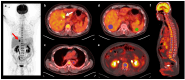

2-Deoxy-2-[18F]fluoro-d-glucose (FDG) uptake of the reticuloendothelial system on positron emission tomography/computed tomography (PET/CT) is known to be related to systemic inflammatory response to cancer cells in patients with diverse malignancies. This retrospective study aimed to investigate whether FDG uptake by the reticuloendothelial system had a prognostic value in predicting progression-free survival (PFS) and overall survival (OS) in 138 cholangiocarcinoma patients. Quantifying FDG uptake of the aorta, bone marrow (BM), liver, and spleen from staging FDG PET/CT images, we found significant correlations between the BM-to-aorta uptake ratio (BAR), spleen-to-aorta uptake ratio, and BM-to-liver uptake ratio with tumor stage and serum inflammatory markers. In the multivariate survival analysis, BAR was an independent predictor of PFS (p = 0.016; hazard ratio, 2.308) and OS (p = 0.030; hazard ratio, 2.645). Patients with stages III-IV of the disease and a high BAR exhibited low 1-year PFS (35.8%) and OS (60.2%) rates, while those with stages I-II of the disease and low BAR showed robust rates of 90.0% and 96.7%, respectively. BAR measured on staging FDG PET/CT might be a potential imaging biomarker offering insights into the systemic inflammatory response and predicting prognosis in cholangiocarcinoma. This study highlights BAR as a promising, independent predictor with potential for personalized prognostication and treatment strategies.